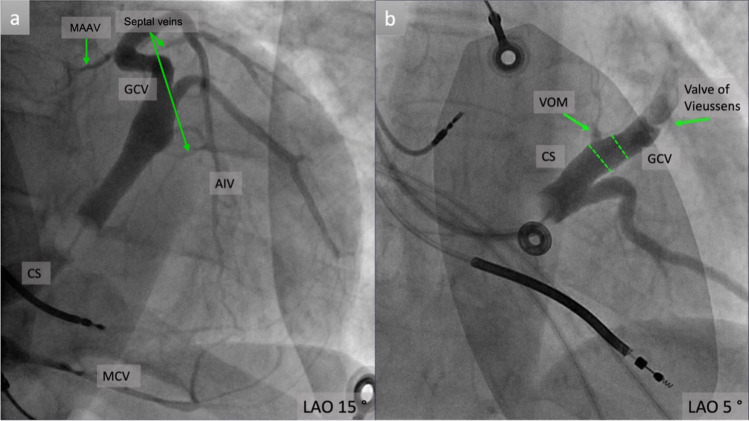

Purpose of review: This review aims to synthesize current knowledge on the angiographic anatomy of the coronary sinus and its tributaries veins, with focus on venous branches other than classical ones used in cardiac resynchronization therapy. It also presents common anatomical aspects that could impact the clinical outcome.

Recent findings: Recent advancements in the electrophysiology field, like epicardial arrhythmia mapping and ablation through coronary sinus or cardiac pacing from atypical veins requires a detailed angiographic assessment of cardiac veins. There is an increased interest for the veins coursing in the left ventricular summit (LVS) area and could potentially provide a pathway to reach the LVS arrhythmogenic foci. However, there is no consensus regarding the nomenclature and classification of these veins. This review could offer a better understanding of the coronary sinus and its tributary veins distribution, dimensions and relationship with nearby structures that could help the development of new ablation and pacing tools and strategies, with higher success rates.